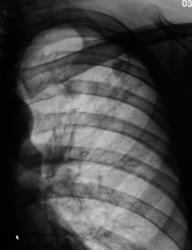

2._EGO..JPG